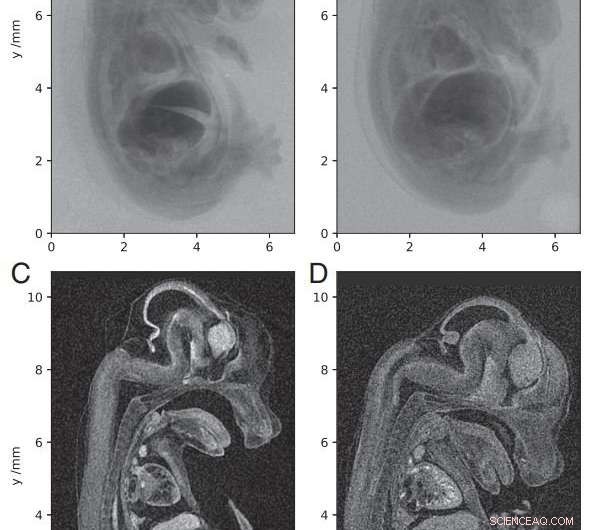

Tomographic imaging of a 14.5-dpc mouse embryo. (A–D) Single X-ray projections (A and B) and sagittal slices from 3D reconstruction (C and D). A and C were acquired with the laser-betatron source and B and D with a commercial microfocus scanner. Credit: Proceedings of the National Academy of Sciences https://doi.org/10.1073/pnas.1802314115

One of the most vital research paths in genetics is the relationship between genes and embryonic growth. Noninvasive, whole-body 3-D imaging of embryos is highly important for establishing these relationships in order to determine the impact of specific genes on development. Mice are a widespread research model in genetics, but capturing 3-D imagery of mouse fetal development requires higher resolution and higher throughput than conventional micro computed tomography (micro-CT) can provide.

Plasma acceleration is a technique for accelerating charged particles using high-gradient plasma structures. In this case, the radiation was generated by the betatron motion of electrons inside a dilute, transient plasma, which overcame the limitations of previous micro-CT radiation sources using conventional solid or liquid anodes. "We show that with the laser-betatron source, we obtain embryo images of quality equivalent to that of the benchtop scanner but with a single laser pulse rather than the multi-second exposure required with the X-ray tube," the authors write.

They report that their device has a higher photon energy than that used to demonstrate phase-contrast tomography of insect samples. They have increased the X-ray penetration depth and improved the signal-to-noise ratio, resulting in images of higher quality than those produced by commercial microfocus scanners.